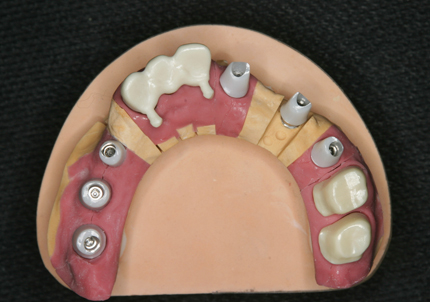

6.インプラントシリンダーテック作製

7.最終補綴作製(前歯部アバットメント装着)

8.ジルコニアフレーム、アバットメント試適

9.セラミック焼成